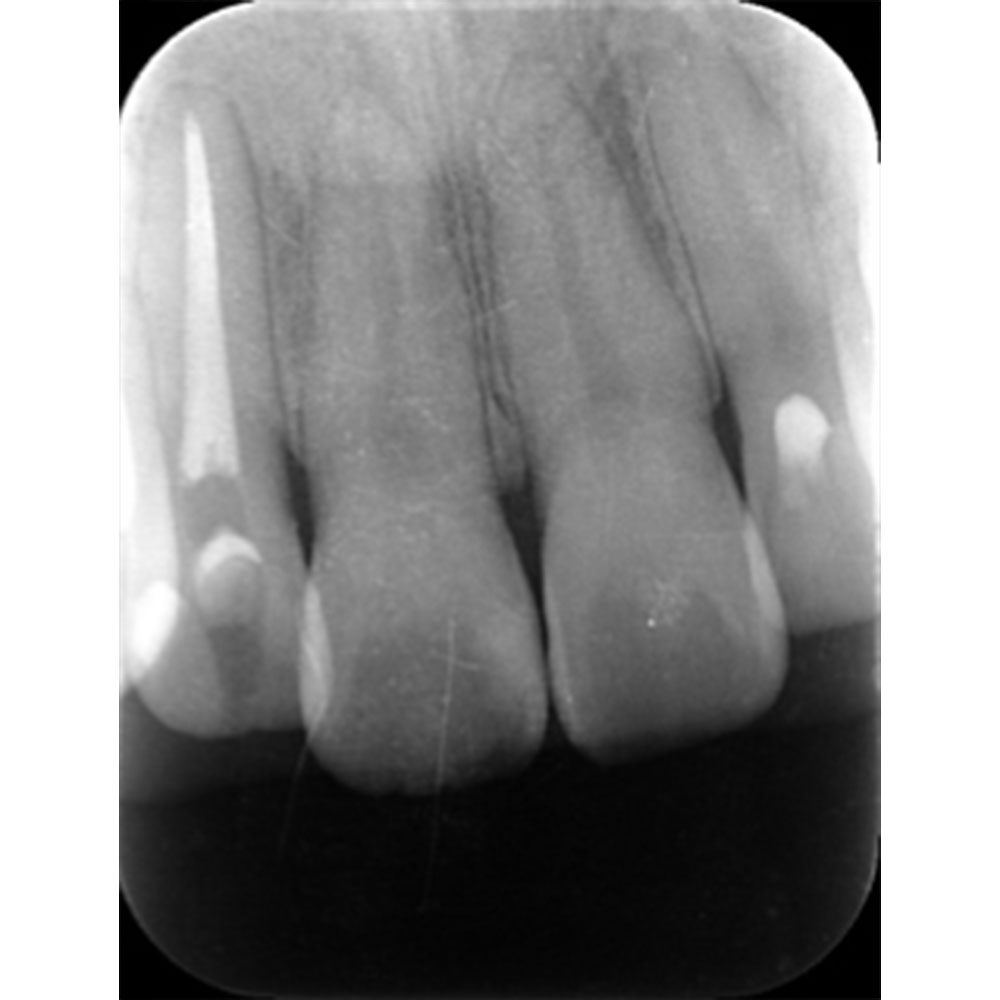

歯の根の治療は難しいことは先述しましたが、歯の内部からの治療だけでは治らないことがあります。

それは歯の先に枝分かれが多く存在し、そこにばい菌が入り込んで難治性となっているからです。ではその場合どうするのか?外科治療をします。その枝分かれの部分を切り落とすのです。今回はその前後のレントゲンの写真をお見せします。

| 根の中の薬が十分に充填されておらず、根の先が周りと比べて黒くなっており、炎症があると判断できます。 | 根の中にしっかりとお薬を緊密に充填しましたが、まだ根の先に黒くなっている部分があります。 |